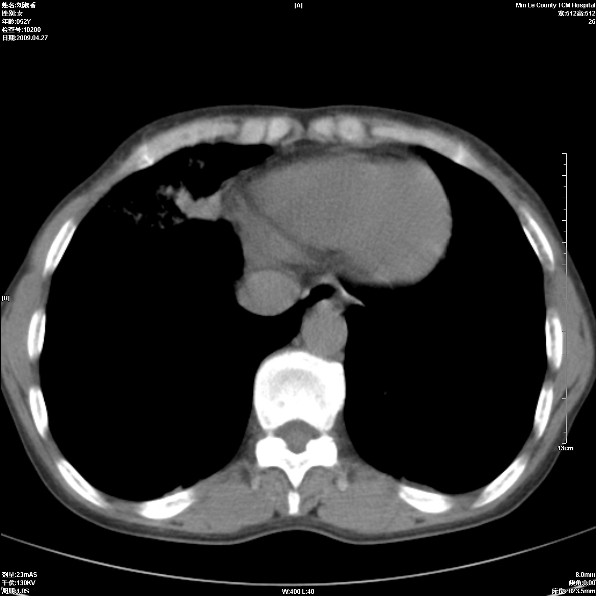

标题: CT19625:女52间断性喀血 [打印本页]

标题: CT19625:女52间断性喀血

考虑右肺中叶感染性病变并右肺中、下叶肺泡积血;建议抗炎、止血治疗后复查。

右肺中叶炎症;右肺中、下叶肺泡积血

右肺中叶支气管扩张并感染或咳血沉积,块右肺中下叶肺泡积血。

右肺中叶慢性炎症伴局部支扩并中下叶肺泡积血。

考虑右肺中叶感染性病变并右肺中、下叶肺泡积血。建议治疗后复查。